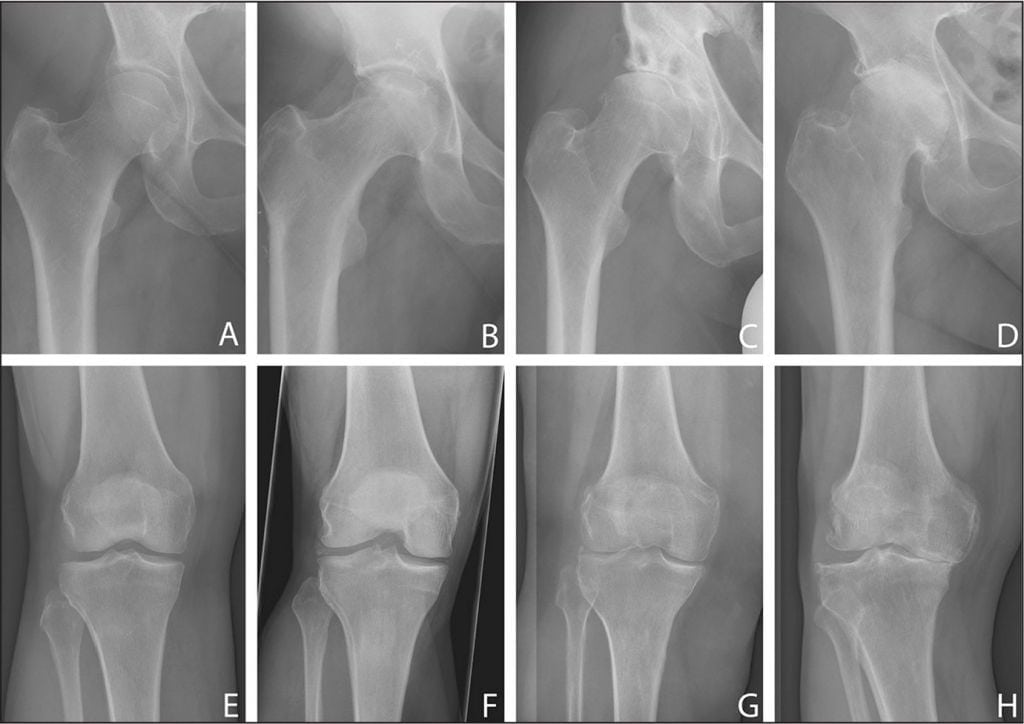

- Гонартроз 1 степени характеризуется повышенной утомляемостью конечности. Кость на этом этапе не претерпевает значительных изменений, однако, едва заметное ограничение движения все же присутствует. Эта степень также характеризуется некоторым сужением суставной щели, которое можно увидеть только на рентгеновском снимке.

- Гонартроз 2 степени сопровождается болевыми ощущениями после нагрузки сустава: во время ходьбы больной слышит хруст в колене. Он не может согнуть или разогнуть сустав полностью. Боль может наблюдаться перед началом движения (стартовая). На снимке заметно сплющивание краев костей.

- Гонартроз 3 степени характерен сильной болью, которая чувствуется, даже если человек находится в состоянии покоя. В пораженной области может возникать отек и повышаться температура. Сустав становится нестабильным, может резко заклинивать.

- Рентгенографию сустава. Тут можно увидеть степень сужения суставной щели, повреждение хряща и кости, наличие скопления солевых отложений, остеофитов.